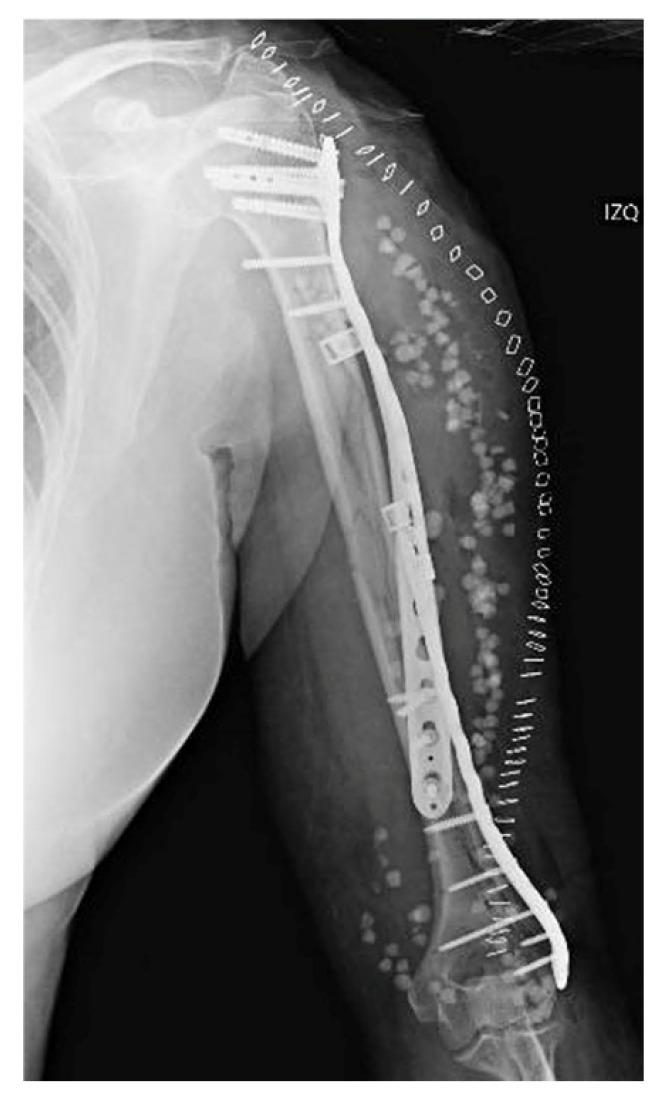

: Non-prosthetic peri-implant fractures (NPPIFs) are rare injuries occurring around internal fixation devices, and are distinct from periprosthetic fractures. While most studies focus on the femur, humeral NPPIFs remain poorly documented. This case illustrates a complex humeral NPPIF and highlights key surgical considerations. : A 62-year-old woman presented with a spiral humeral shaft fracture (AO 12B2) after a fall. Following closed reduction and antegrade intramedullary nailing, an intraoperative peri-implant fracture occurred at the distal interlocking screw. CT imaging revealed a complex fracture extending from the lateral condyle to the proximal humerus. Treatment included implant removal and open reduction with dual plate fixation-lateral distal and helically contoured proximal plates-plus cerclage bands and antibiotic-loaded beads. Recovery was uneventful, with a full range of motion achieved at six months. At one year, the DASH score and MEPS were 86 and 75, respectively. : Humeral NPPIFs are challenging and require individualized, biomechanically sound strategies. This case reinforces the importance of intraoperative assessment and careful implant selection in humeral fracture management.

非假体周围植入物骨折(NPPIFs)是发生在内固定装置周围的罕见损伤,与假体周围骨折不同。虽然大多数研究集中在股骨,但肱骨NPPIFs的文献记载仍然很少。本病例说明了一例复杂的肱骨NPPIFs,并强调了关键的手术注意事项。一名62岁女性在跌倒后出现肱骨干螺旋骨折(AO 12B2)。在进行闭合复位和顺行髓内钉固定后,术中在远端锁定螺钉处发生了植入物周围骨折。CT成像显示骨折复杂,从外侧髁延伸至肱骨近端。治疗包括取出植入物,采用双钢板固定(外侧远端钢板和螺旋形近端钢板)、环扎带和载抗生素骨珠进行切开复位。恢复过程顺利,六个月时实现了全范围活动。一年时,DASH评分和MEPS分别为86和75。肱骨NPPIFs具有挑战性,需要个体化的、生物力学合理的策略。本病例强化了术中评估和在肱骨骨折治疗中谨慎选择植入物的重要性。